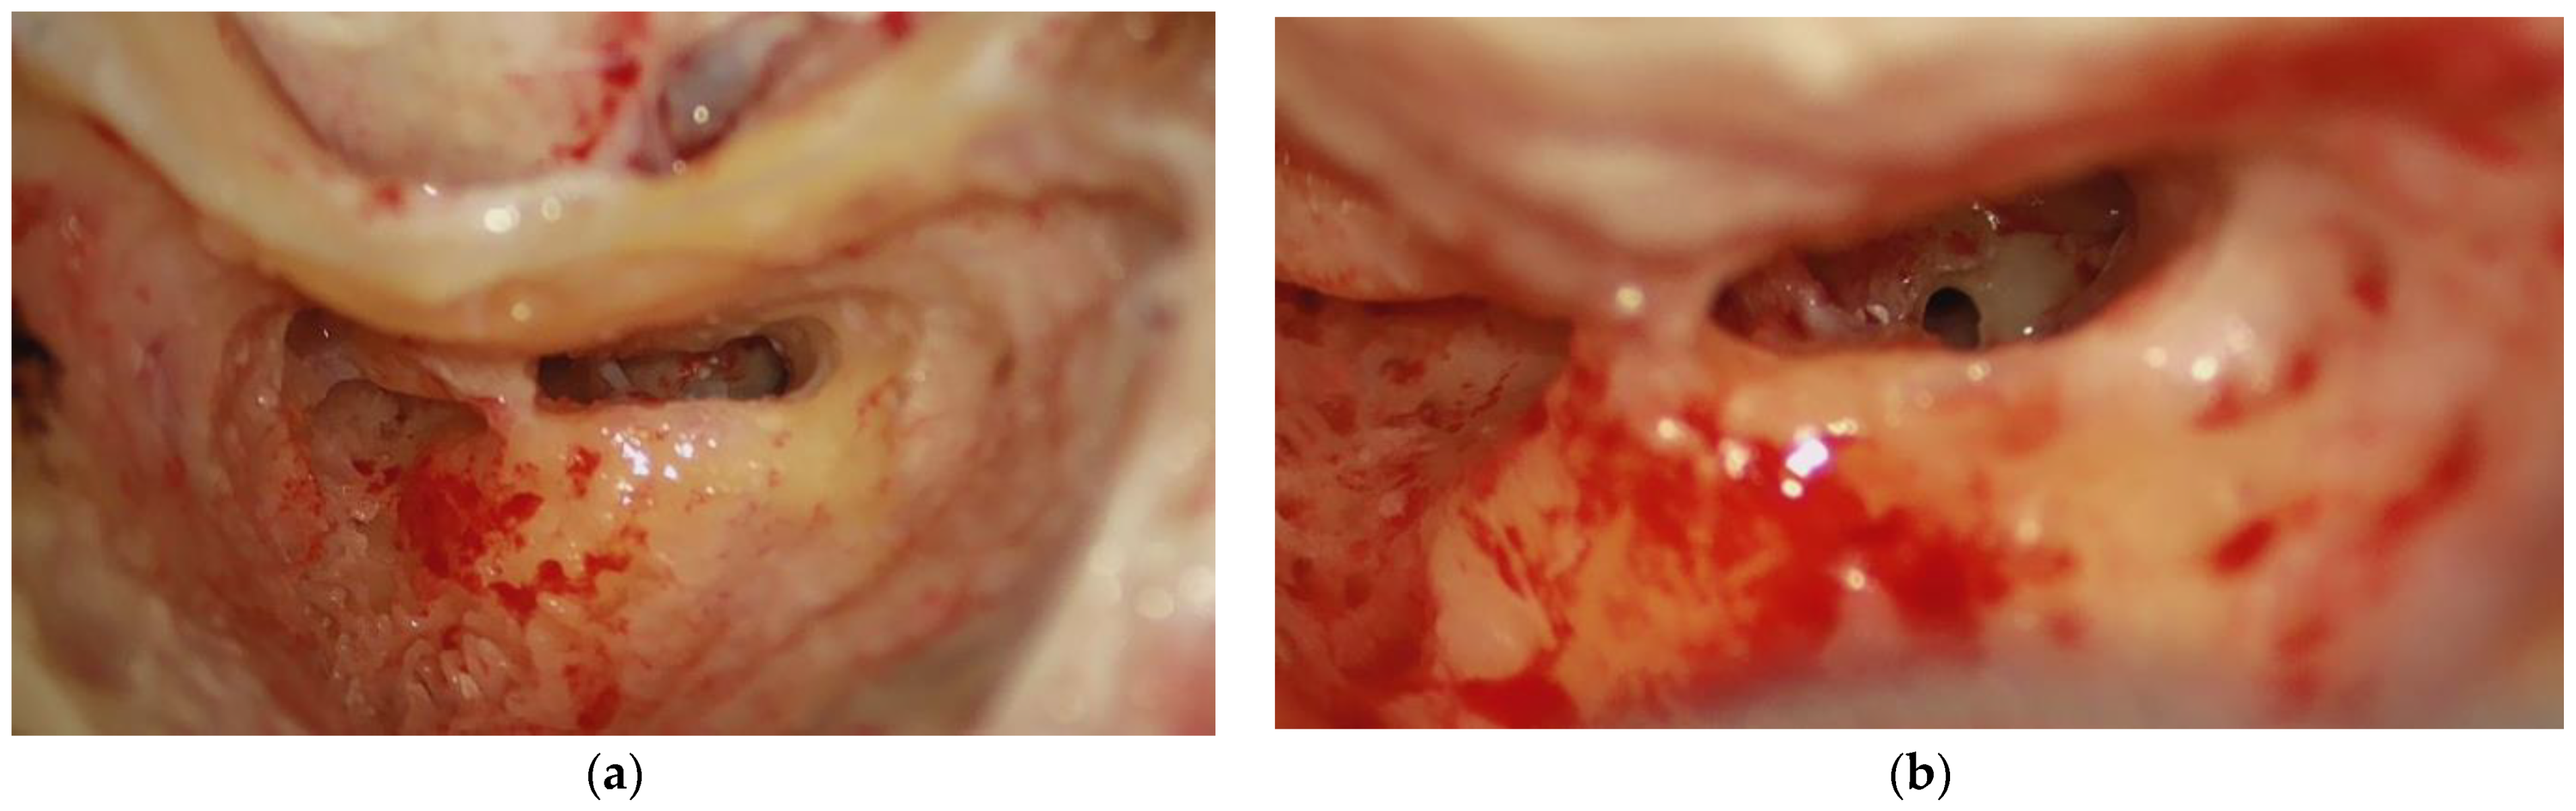

The patient is operated on lateral decubitus, on the contralateral side to the surgical site. The stabilization is guaranteed by supports placed posteriorly over the sacrum and another cranial at the scapular level. If the patient’s stability is not well obtained, an anterior fixator must also be used, over the pubic symphysis or the ipsilateral anterior superior iliac spine (Figure 3a,b) [9]. The upper limb, on the same side as the surgery, is fixed anteriorly over a support perpendicular to the chest. The contralateral upper limb can be left alongside the body or extended like the ipsilateral limb to allow further access available to the anesthetist. In this position, cervical spine stiffness is no longer a problem, and furthermore, no rotation of the operating table is necessary.

Figure 3. Patient stability in “hip replacement surgery” [9]. (a) The anterior support is placed over the pubic symphysis or (b) over the anterior superior iliac spine.